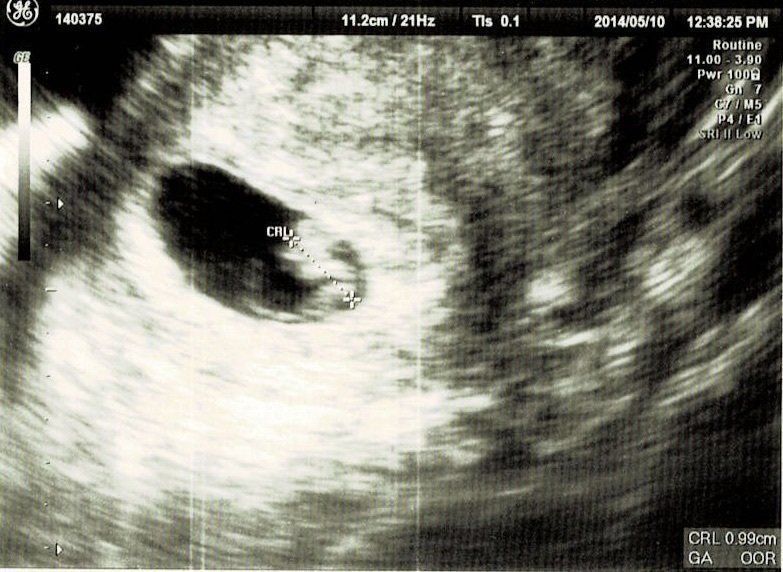

妊娠8週目エコー写真

妊娠10週目エコー写真

職場の上司にはこの時点で報告しておきました。「もし、妊娠が継続しなかったら……」ということも考えたのですが、早く伝えたほうが会社にも迷惑がかからないだろうと考えました。このとき、初めて心拍が確認できました。診察後産院の受付に行くと、「赤ちゃんに会える日を楽しみにしています」と書かれたメッセージカードを頂きました。中を開くとエコー写真が。大感激して、今でも大切に取ってあります。